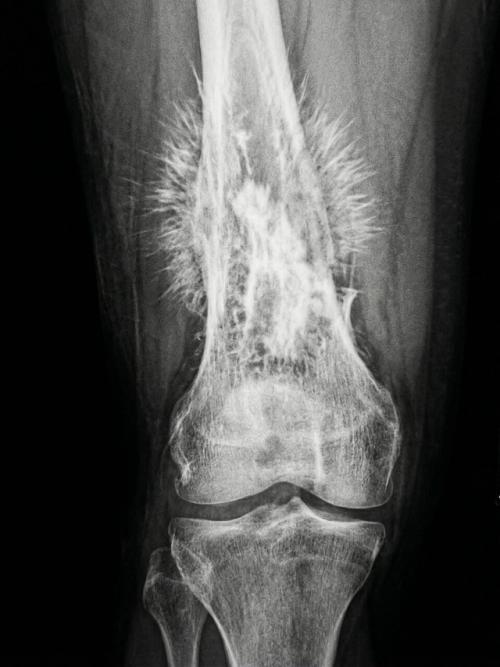

Остеосаркома - это агрессивный рак костной ткани. Один из самых тревожных признаков на таких изображениях - так называемые спикулы, или игольчатый периостоз. На снимке кость будто покрывается острыми "Лучами", и выглядит это так, словно организм уже не просто болеет, а буквально кричит о беде.

Для онкологов и рентгенологов такая картина - не просто деталь, а сигнал очень тяжёлого процесса. Подобные изменения часто указывают на то, что опухоль ведёт себя быстро, жёстко и не оставляет времени на долгие раздумья.

Именно поэтому в подобных случаях всё решает скорость: не "Понаблюдать Потом", не "подождать до следующей недели", а действовать сразу. Потому что иногда на снимке видна уже не просто проблема, а гонка со временем.